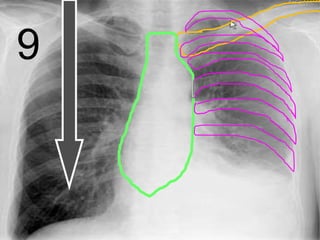

Sternum

Clavicle

9

Ribs